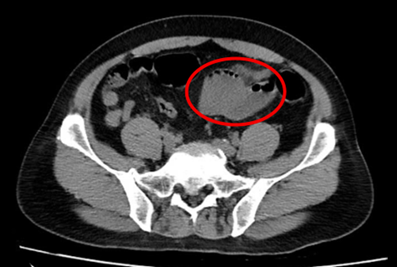

– Chụp cắt lớp vi tính ổ bụng (11/07/2025) – trước phẫu thuật:

Hình 1: Hình ảnh chụp cắt lớp vi tính ổ bụng: Quai hồi tràng vùng hạ vị dày thành không đều, tạo khối kích thước 49x47mm (vòng tròn đỏ), thâm nhiễm mỡ xung quanh, ngấm thuốc mạnh đồng nhất sau tiêm.